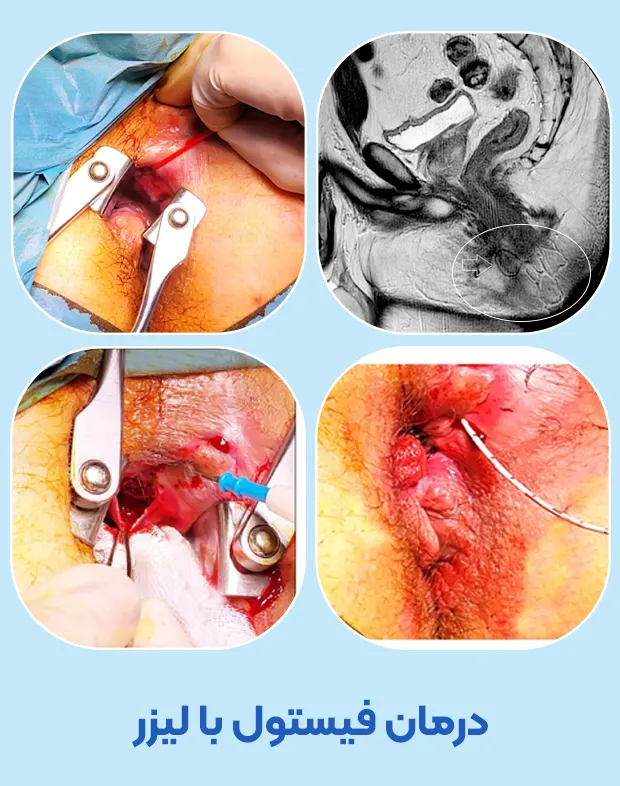

درمان فیستول با لیزر

در درمان فیستول با لیزر نیازی به بیهوشی نیست و با بی حسی ناحیه مقعد فیستول را لیزر می کنند. طی عمل لیزر فیستول ابتدا مجرای فیستول را با مواد مخصوص ضد عفونی و تمیز می کنند بعد لیزر را که از یک سری و یک فیبر نوری متشکل شده است از داخل بافت فیستول به آرامی عبور م دهند. لیزر به آرامی بافت مجرای فیستول را التیام می بخشد و از بروز عفونت در آینده پیشگیری می کند.

طی یک جلسه لیزر به صورت سرپایی حدود نیم ساعت می تواند انواع فیستول مقعدی را درمان کرد. درمان فیستول با لیزر با کمترین درد و خونریزی انجام می شود و احتمال عود فیستول در آینده نسبت به روش های سنتی بسیار پایین است.

لیزر از نور بدون خطر مادون قرمز برای التیام بافت و بسته شدن مجرای فیستول استفاده می کند. پس نگران لیزر نباشید چرا که این لیزر بی خطر بوده و در درمان فیستول با موفقیت عمل می کند.

فیلم درمان فیستول با لیزر

در زیر دو فیلم نحوه لیزر فیستول مقعد را می توانید مشاهده فرمایید.